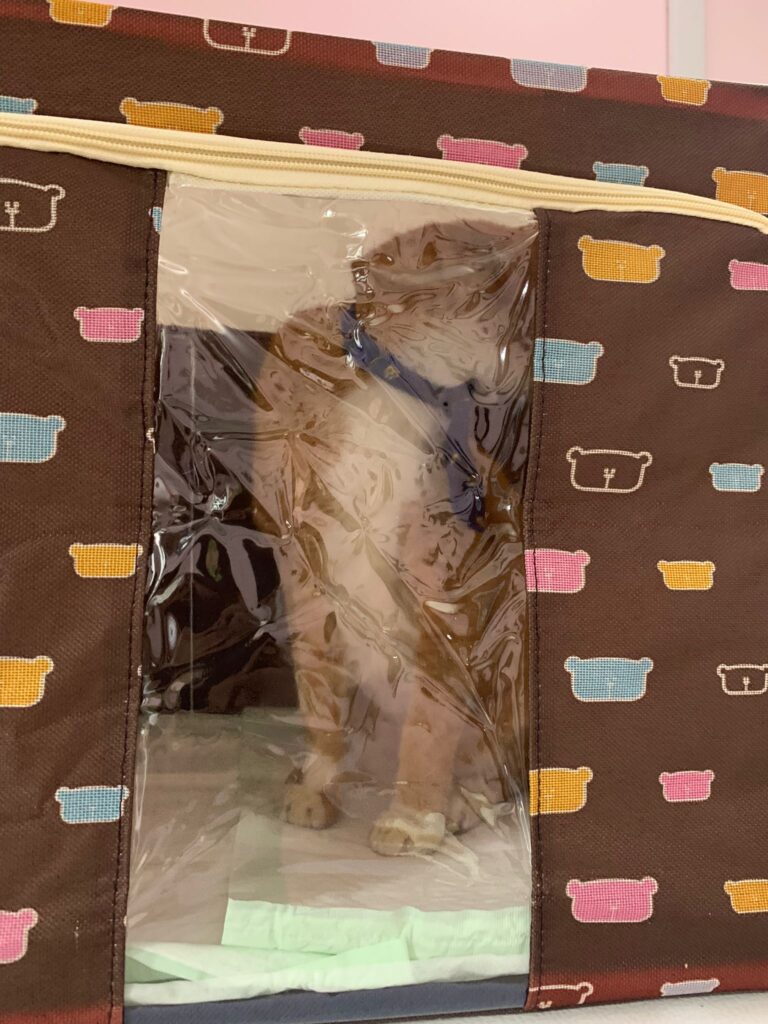

Morning: he is fine, didn’t hear him cough or sneeze. He is eating well. today I started nubulizing him, set up a bear box in 5G for his nubulizing. he did meow but not any extreme reaction in there. Wow smoky when I open up to let him out. think can do that for Jack or so when I’m in longer hours.

Didi 4.9.22 Thurs

Day: today nubulize him again day 02 – Quite steady already. 🙂